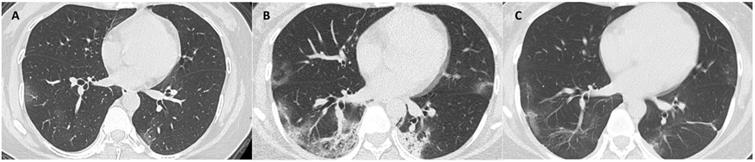

The median days of illness since symptom onset for the first, second and third milestones were 2 (range: 0-12), 10 (1-22), and 22 (7-53), respectively. The median values of total CT scores, and the mean values of each laboratory parameter at 3 milestones are listed in Table 3. Serial CT images at 3 milestones in 2 patients are shown in Figure 1-2.

Figure 2

CT scans at 3 milestones in a 33-year-old woman with COVID-19 pneumonia. (A) Initial CT obtained on illness days 7 showed ground-glass opacity in bilateral lower lobe. (B) Worst CT obtained on illness days 13 showed ground-glass opacity and consolidation with largely increased extent in bilateral lower lobes. (C) CT scan before discharge obtained on illness days 22 showed mild residual ground-glass opacity. The patient was discharged on illness days 25.